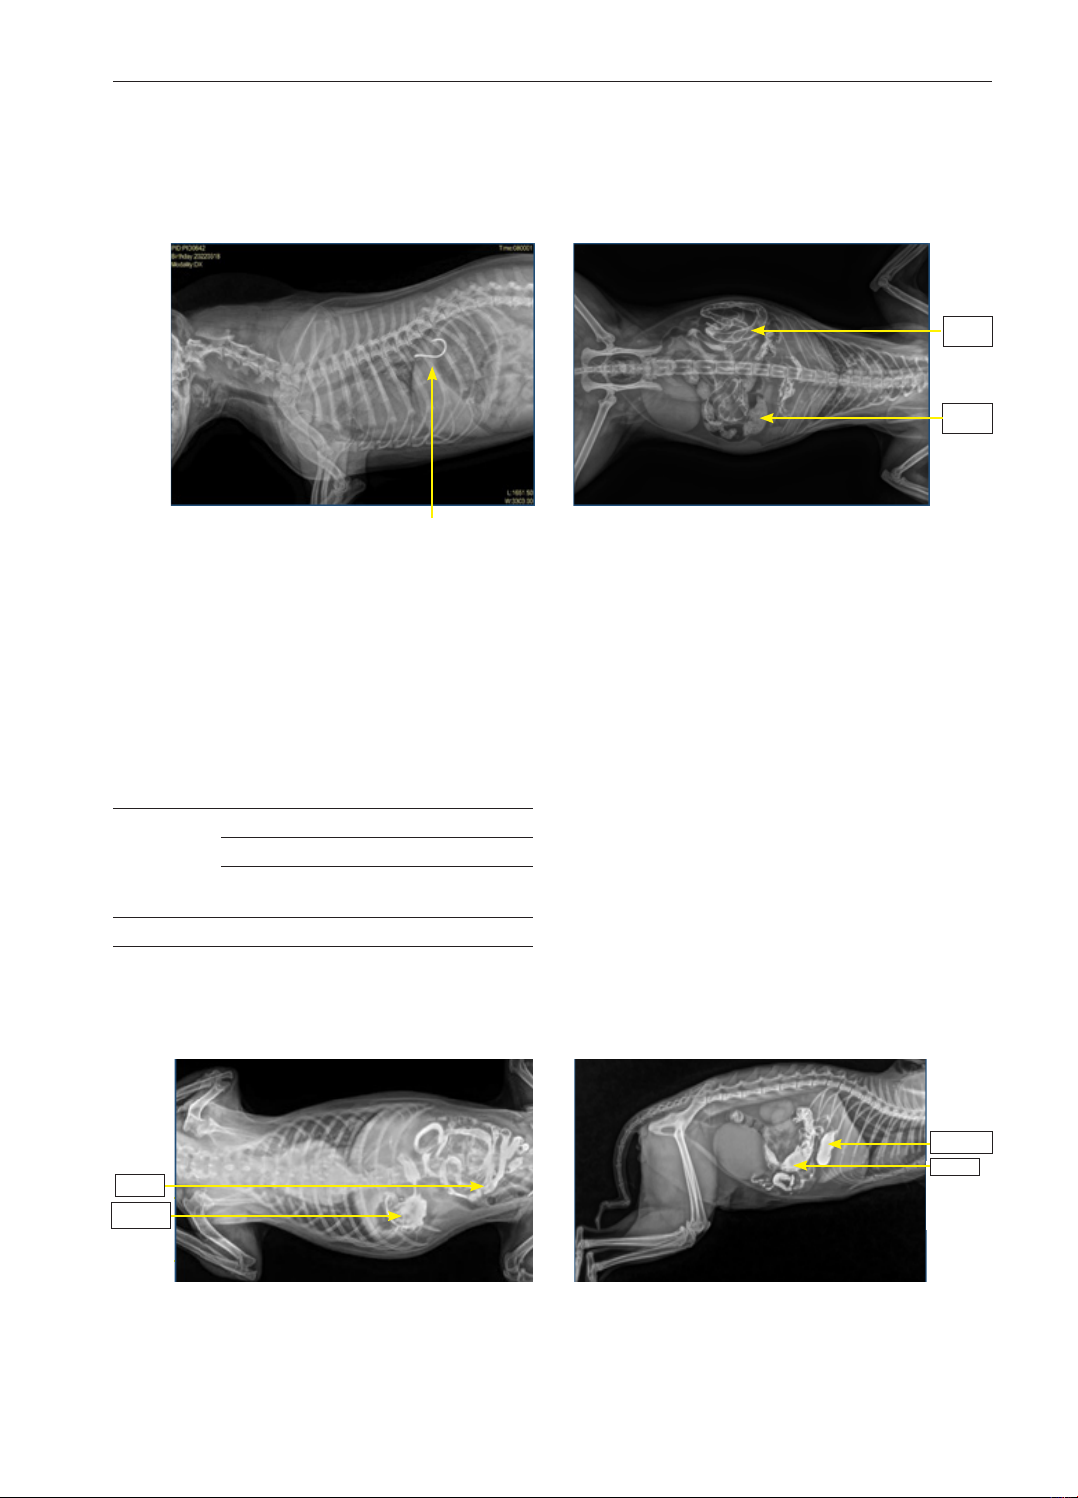

Hình 1. X-quang thấy dị vật

móc câu ở dạ dày Hình 2. X-quang thấy ruột rất nhiu khí

và chứa nhiu đoạn phân nghi ngờ táo

Dạdày

Ruột

Hình 3. X-quang thấy dạ dày chứa nhiu khí

và cn quang chy đu ở ruột Hình 4. X-quang thấy hình thái dạ dày bình

thường nhưng có đoạn quai ruột phình to